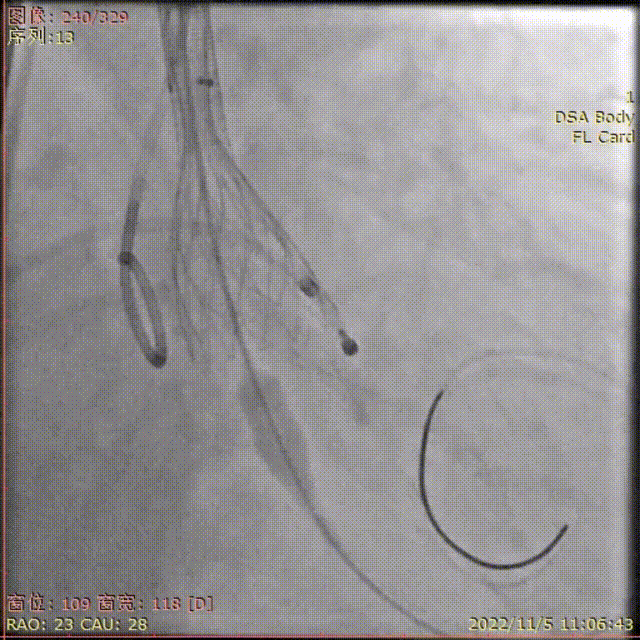

术中影像

主动脉根部造影

导丝顺利跨瓣

TaurusElite输送器顺利过弓

瓣膜初始定位

瓣膜稳定释放到工作位,无位移

工作位多角度评估

瓣膜完全释放